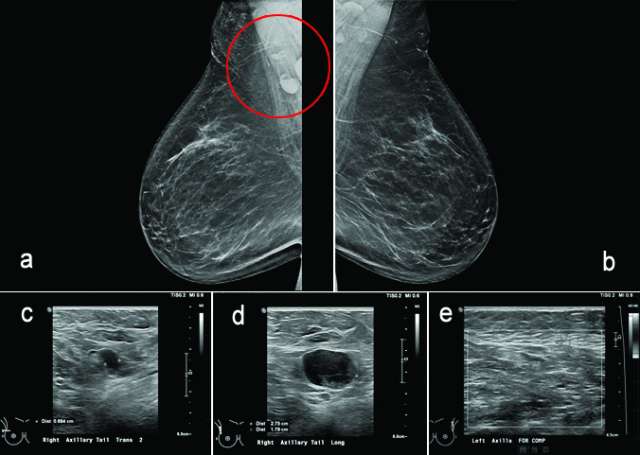

Figure 6, a-e.

Case: Axillary Lymphadenopathy  Figure 6

Figure 6: 61-year-old female with no significant past medical history called back from screening mammogram for prominent right axillary lymph nodes (figure 6a, red circle). Bilateral axillary ultrasound was performed showing enlarged lymph nodes with increased cortical thickness (figure 6c) and replaced fatty hilum (figure 6d). No abnormal lymph nodes in the left axilla were identified (figure 6e). Lymph node biopsy was recommended for BIRADS category 4B. Biopsy results are pending.